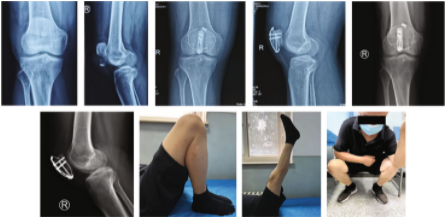

图3. 对照组和实验组患者复位前后的比较。

a - f : 38岁,男性,入院前3小时因摔伤导致骨折入院。a-b术前CT检查矢状面。c-d术前冠状面CT检查。e-f术后x线片。

g-l:一名65岁女性,入院前5小时因跌倒导致骨折。g-h术前矢状面CT检查。i-j术前冠状面CT检查。k-l术后x线片。